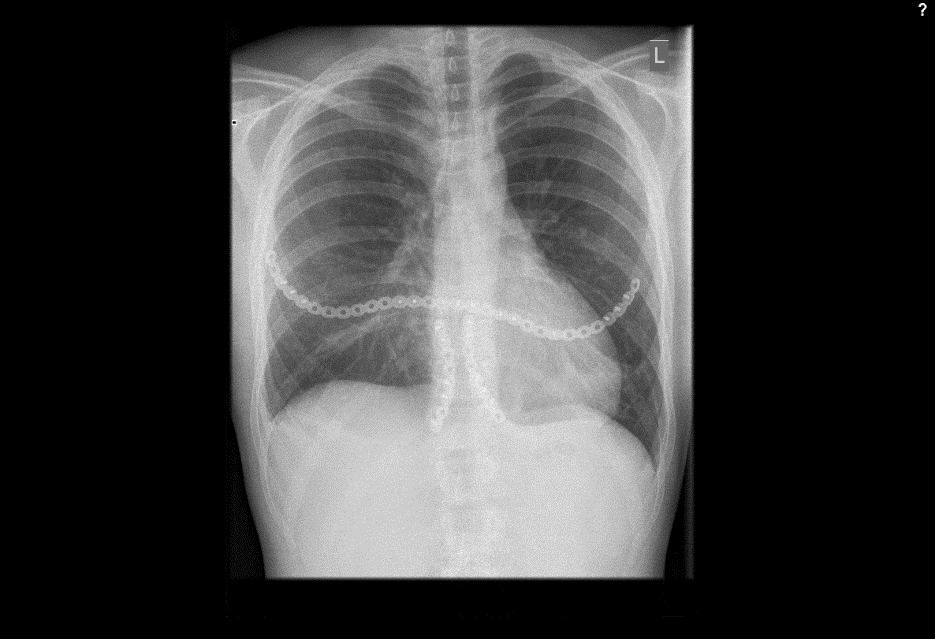

Case image provided by W Long, Portland, OR

Fall from 4-meter height

Mechanism of injury: An 81 year old woman fell onto her back from a height of 4 meters. (Fig 6a-d) She sustained a multiple sternal fracture concomitant with a fracture of the 5th thoracic vertebra resulting in an unstable injury of the trunk. Fortunately she did not show any neurologic deficit or paraplegia.

Diagnosis: Complex sternal fracture with multidirectional instability (longitudinal fracture of the manubrium, transverse fracture involving 3 levels of manubrium and corpus sterni) Concomitant to this was a fracture of the 5th thoracic vertebra (AOB2.1).

Treatment: The sternal fracture has been managed by open-reduction and internal fixation with a locked plate osteosynthesis (MatrixRIB, I-Plate) through an anterior approach in the mid-line. b The thoracic spine has been managed employing dorsal instrumentation (internal fixator th4-th6).

Post-operative outcome: The wounds and bone healed uneventfully. Breathing was possible spontaneously without any restrictions. The patient reported on a significant reduction of the pain immediately after the operative procedure. Mobilization on the ward started on the first day after the procedure. No complications such as secondary failure, non-unions, pain or deformity of the chest wall could be seen during the follow up examinations of 6 and 12 weeks and 6 and 12 months.